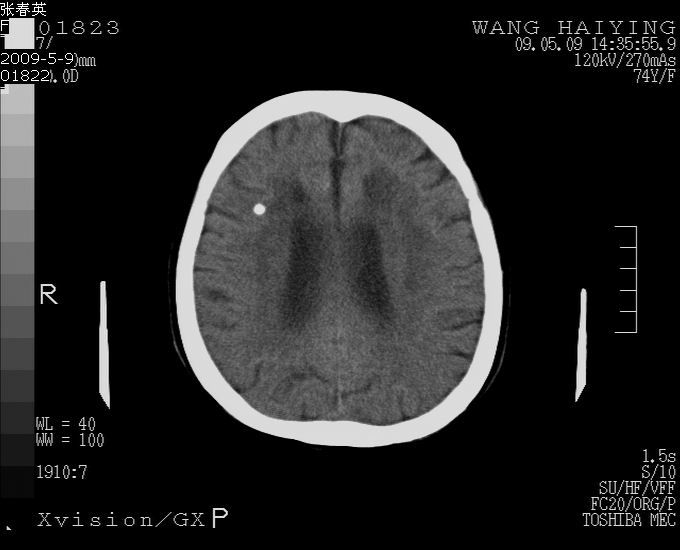

以下是引用余辉在2009-5-9 18:32:00的发言:[br]基底动脉稍扩张且右偏,其上方层面见高密度块影,考虑动脉瘤可能,建议增强,皮脑

以下是引用杀毒软件在2009-5-9 17:48:00的发言:[br]不排除动脉瘤可能,建议进一步检查。 [br]